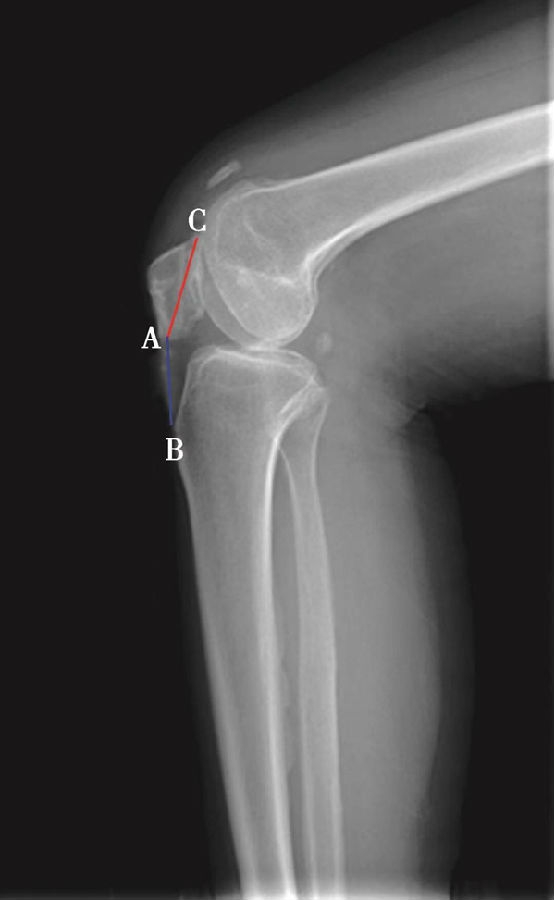

如图示:AB为髌骨关节面最低点到胫骨平台轮廓前上角最短的距离,AC是髌骨关节面的长度。Caton指数=AB/AC(图1)。

图1

图2 Caton指数=AB/AC=1.10,为正常髌骨高度

临床工作中常常使用其来估计胫骨结节移位的效果。正常人的Caton指数=1,正常范围0.8~1.2(图2)。需要注意的是:术前规划胫骨结节需要移位的理论距离为AB-AC,这就是需要将胫骨结节向远端移位的最大距离。但在术中胫骨结节转移的距离往往要小于这个距离,避免因过度移位造成医源性的低位髌骨。